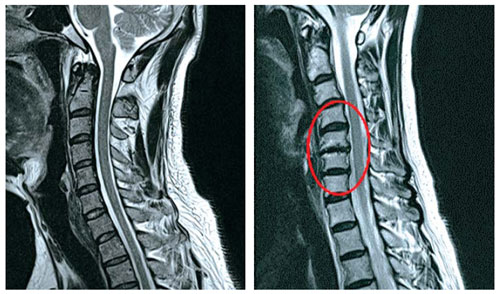

목은 목뼈(경추) 7개로 되어 있다며 뼈와 뼈 사이에 디스크가 있습니다. 디스크는 기립 자세에서 수직으로 끼치는 압력을 분산하고 목이 동작할 때 관절 역할을 합니다. 나이가 들면 아무라도 피부 탄력이 감퇴하여 주름이 생기듯 척추의 디스크도 수분 함유하고 있는 분량이 쇠퇴하여 긴장되고 이로 인하여 충격을 섭식하고 압력을 분산시켜서하는 기능이 저하되요.

목디스크는 왜 생기는 걸까요? 사람들이 나이가 들면 디스크의 수분 성분인 수핵의 수분함유 분량이 떨어뜨리여 탄력이 감소하게 되고 해로운 자세나 사고 등의 바깥 부분적인 자극에 의해 디스크가 밀려나 목디스크 질환의 이유가 되는 것이 된다고 합니다. 평범할 때 생활하면서 틀린 습관, 목에 가해진 충격 등에 의해 일어나기 쉽다고 하고요.